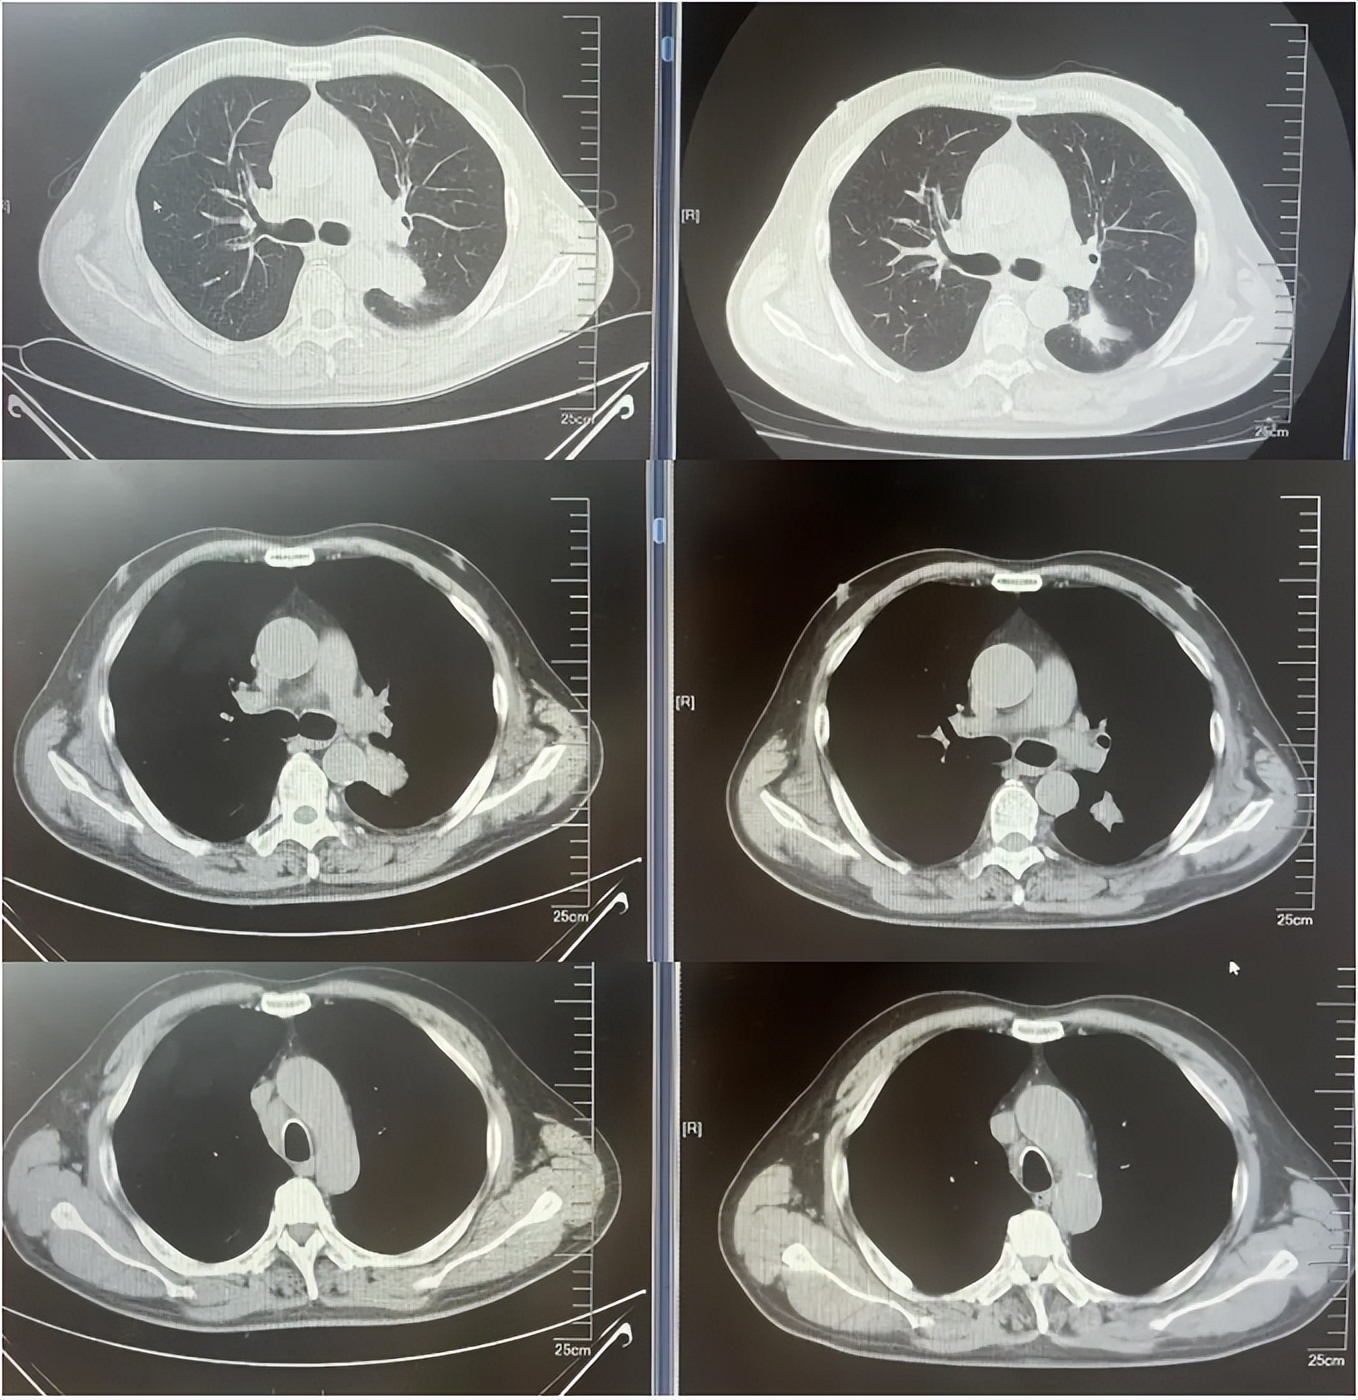

病例1:患者男,68岁。2024年6月以“胸闷气短1个月”为主诉于当地医院检查治疗。查CT提示左肺下叶肿物,纵隔、双肺门多发肿大淋巴结,左侧胸腔积液,左侧胸膜增厚。于当地医院行胸水穿刺引流查癌细胞提示肺腺癌。临床分期:cT2aN3M1a IVA期。患者于当地医院行血液基因检测未见敏感突变,使用AP方案化疗后病情进展。2025-1入我院后行肺穿刺活检,病例提示腺癌。行基因检测提示:ERBB2突变(丰度3.5%)。行德曲妥珠单抗(T-DXd)治疗至今。最佳疗效PR,目前持续有效中,PFS已超过7个月。患者使用德曲妥珠单抗期间出现II级恶心呕吐,经对症治疗可缓解。

德曲妥珠单抗治疗4周期(2025.5)疗效对比

德曲妥珠单抗治疗6周期(2025.7)疗效对比

病例1治疗经过